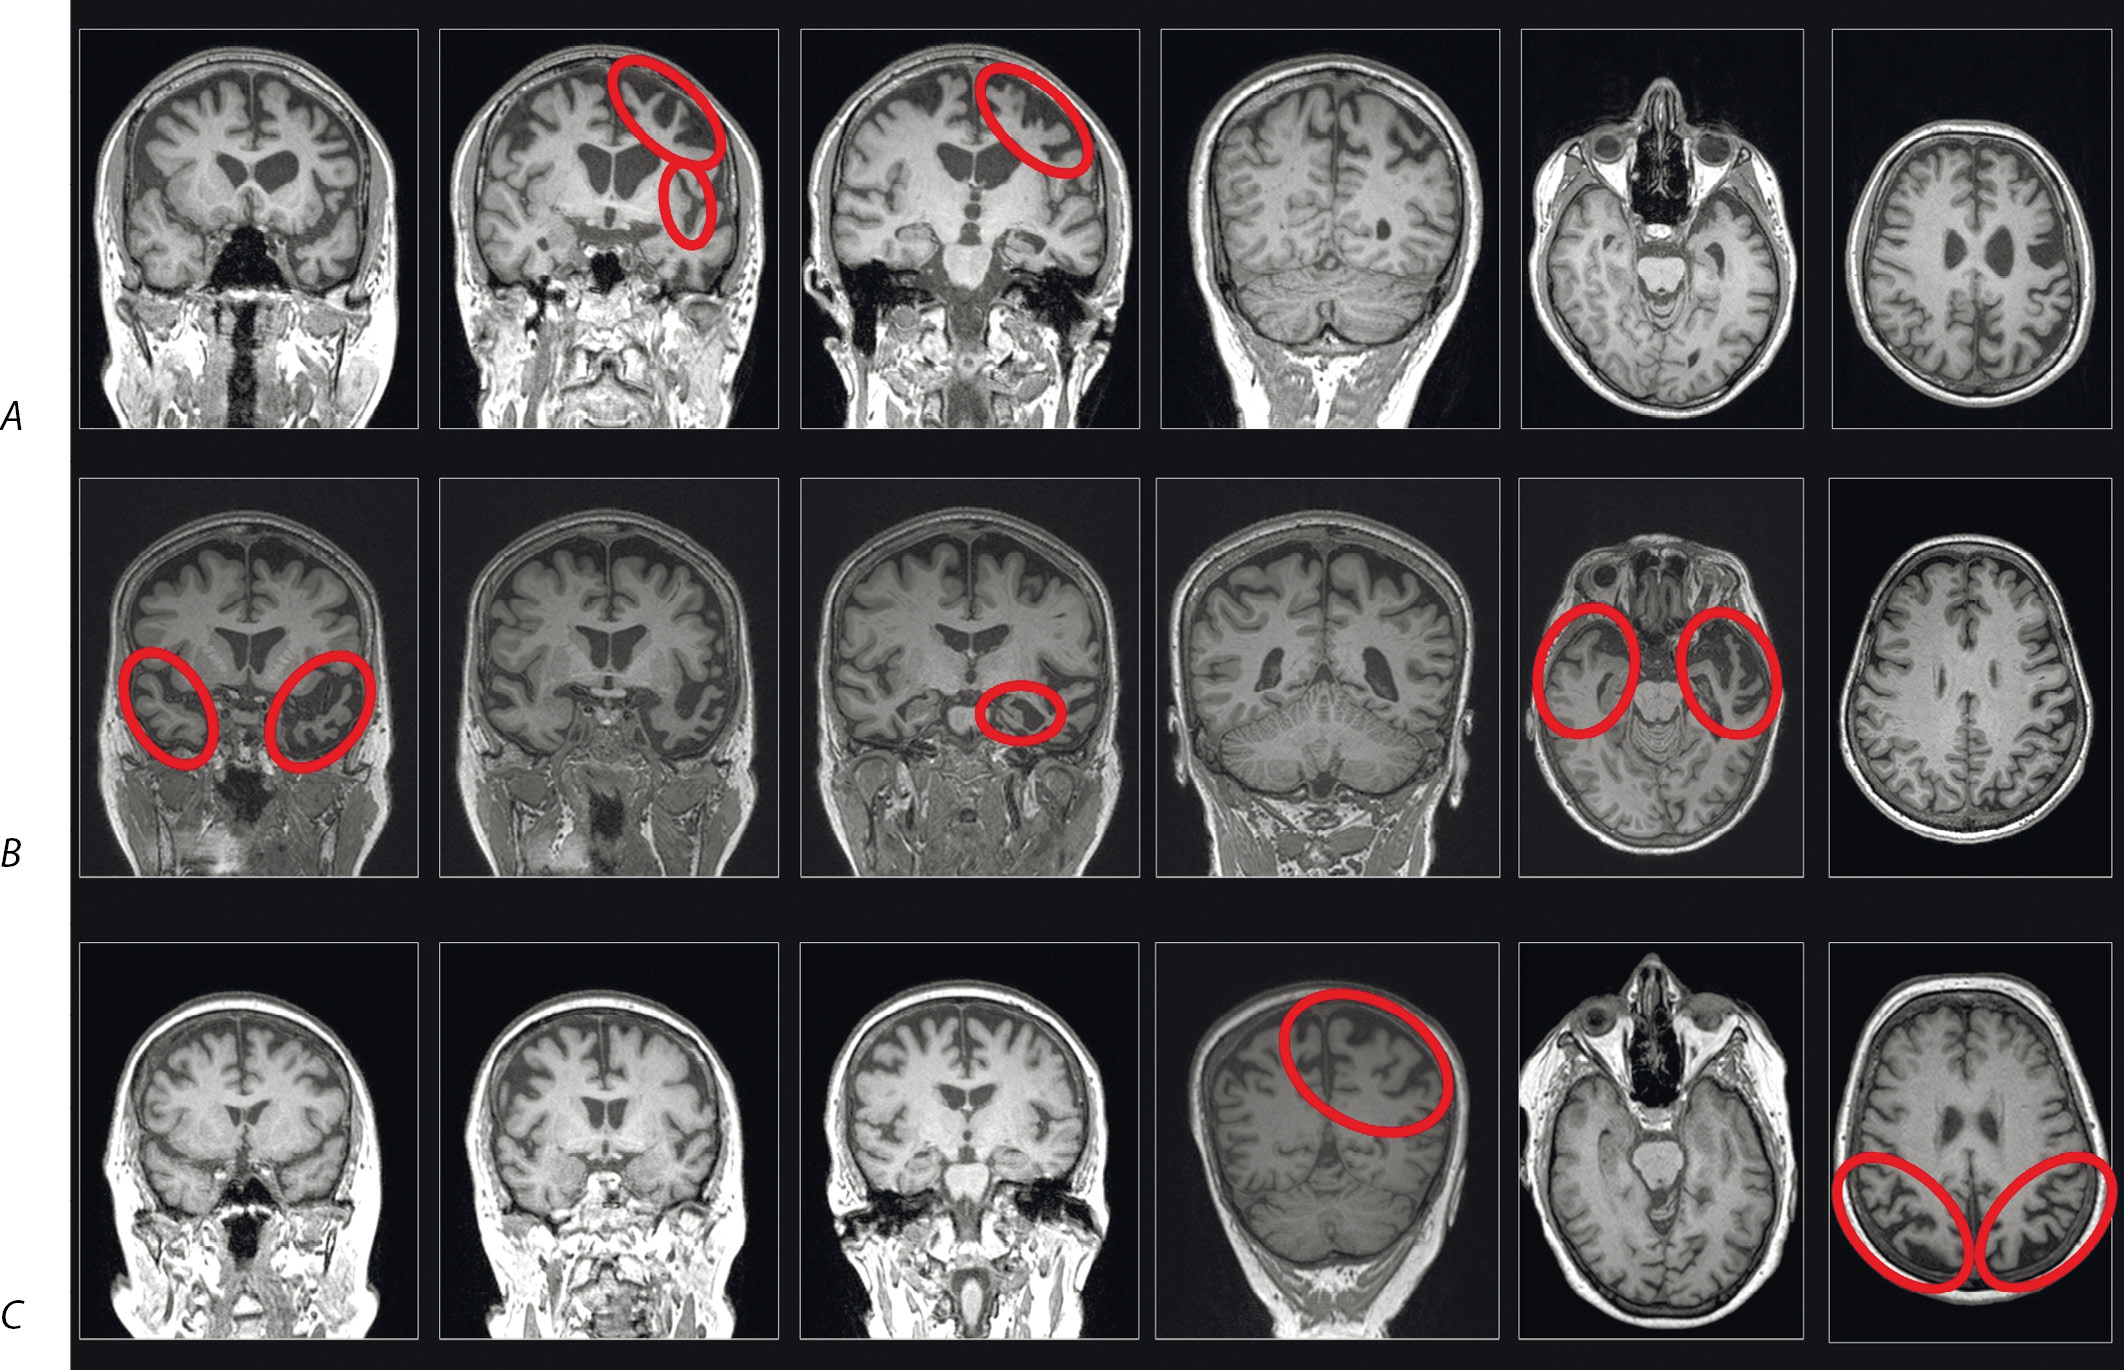

Neurodegenerative aphasia was first described by Arnold Pick in 1892 [2], but the term PPA was introduced only in 1987, when it was proposed to differentiate PPA from Alzheimer's disease (AD) as a distinct disease entity [3]. Initially, PPA was considered to be a single syndrome with a central symptom of anomia, but over time, three clinical syndromes have been identified such as non-fluent (nfPPA), semantic (svPPA), and logopenic (lvPPA) variants. This classification has been used since 2011, when the current diagnostic criteria for PPA were established, describing specific clinical and neuroimaging signs of each variant [1]. The Figure shows examples of PPA from the authors' clinical practice.

Neuroimaging of nfPPA is primarily characterized by atrophy of the left posterior frontal/insular regions (Figure, А), although the process starts affecting other brain regions over time [1, 4]. NfPPA usually develops in patients with frontotemporal degeneration, more commonly with 4R tau inclusions, less commonly with 3R tau or TDP-43, while up to 10% of cases may have an atypical presentation of AD [5, 6]. A positive family history is reported in one third of cases. There are nfPPA cases with mutations across all three major frontotemporal dementia genes such as C9orf72, MAPT, GRN [6].

Atrophy localization in primary progressive aphasia variants.

A — non-fluent variant (patient age 49 years, disease duration 5 years); B — semantic variant (patient age 72 years, disease duration 6 years); C — logopenic variant (patient age 64 years, disease duration 4 years).

The most characteristic areas of atrophy for each of the variants are outlined in red.

Compared to other variants of PPA, svPPA is characterized by the greatest clinical, pathomorphological, genetic, and neuroimaging homogeneity. Anomia and impaired semantic knowledge of objects are the main clinical features of svPPA. In addition, patients may have dyslexia, dysgraphia, and impaired object knowledge. However, fluency and repetition are spared [1]. The atrophy affects the temporal pole, usually the left one (Figure, В). However, in about one-third of cases, atrophy of the right hemisphere predominates, with more severe behavioral disturbances and prosopagnosia in the clinical picture [6]. Pathological studies show that the vast majority of svPPA patients have a frontotemporal degeneration with an abnormal accumulation of TDP-43 type C [5, 6]. Cases with TDP-43 type A or B, tauopathy, or Alzheimer's degeneration are less common. Hereditary forms are less typical for svPPA than for nfPPA. Genetic mutations are found in approximately 2–4% of cases, a positive family history is reported in 2–17% of patients, and most cases are sporadic [27, 28].

LvPPA is characterized by atrophy of the left posterior perisylvian and parietal regions such as the inferior parietal lobule, the temporoparietal junction, and the posterior parts of the temporal lobe (Figure, С), which play an important role in phonological storage [1]. Over time, atrophy may progress to the frontal areas of the brain and the hippocampus, which is associated with additional symptoms of other variants of PPA [68]. The pattern of atrophy also seems to depend on the pathomorphological variant of the disease. In one of the studies, atrophy was more severe in lvPPA with positive AD markers compared with lvPPA without AD markers in the left superior parietal region, inferior temporal gyrus, and more ventral parts of the superior and middle temporal gyri [46]. In general, less studies have been performed to evaluate neuroimaging markers of lvPPA compared with other variants because lvPPA is often considered together with other variants of AD without focusing on language disorders. Available studies of clinical and neuroimaging correlations have shown that naming disorders are associated with atrophy of the middle parts of the left temporal gyrus [33, 52], repetition disorders correlate with damage to the left angular, supramarginal gyri, and posterior parts of the superior temporal gyrus [51], and the rate of phonological speech errors increases with the severity of atrophy of the supramarginal gyrus and inferior parietal lobule [69]. In lvPPA, white matter damage is less severe than in nfPPA and svPPA, affecting only the temporoparietal regions [25].